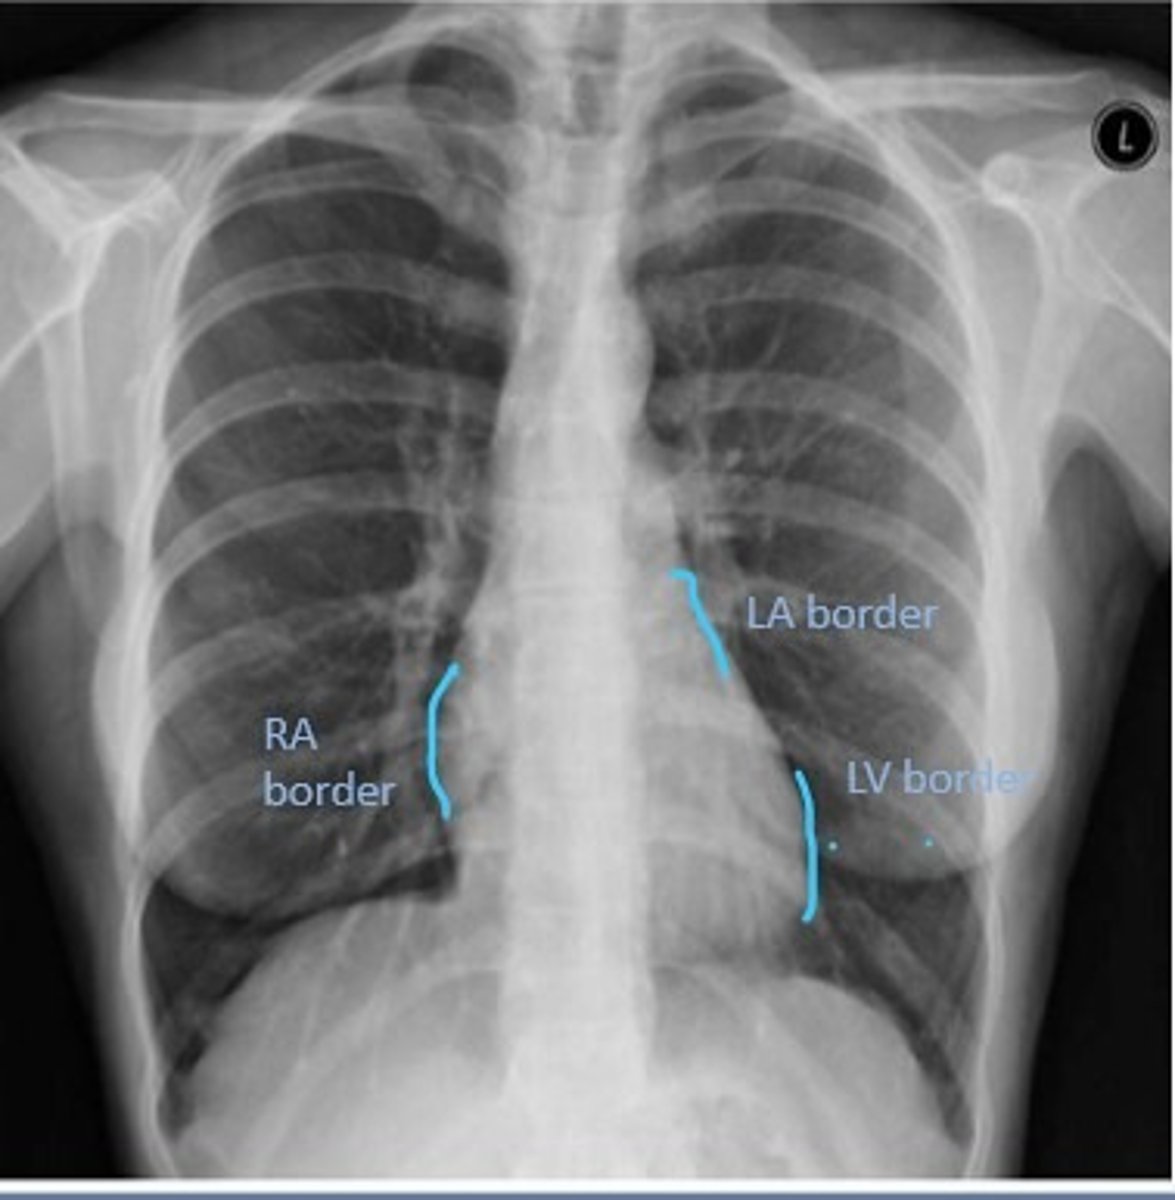

Right Cardiac Border

An area formed by the right atrium

Left Cardiac Border

An area formed by the left ventricle